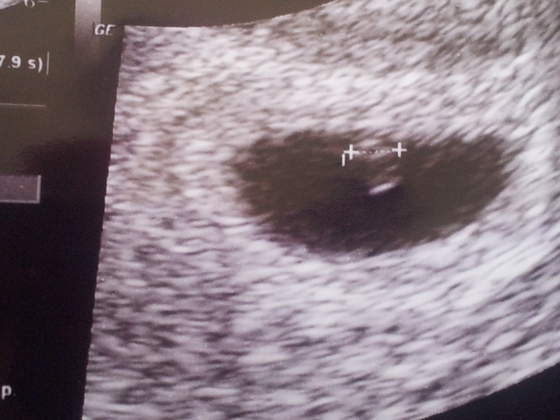

jest dzidzia 3,49 mm

serduszko bije w rytmie czaczanie slychac ale widac